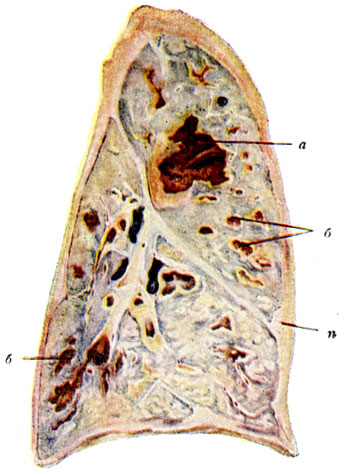

Карнификация Легкого: Микропрепараты и Диагностика

Раздел: Калейдоскоп образов